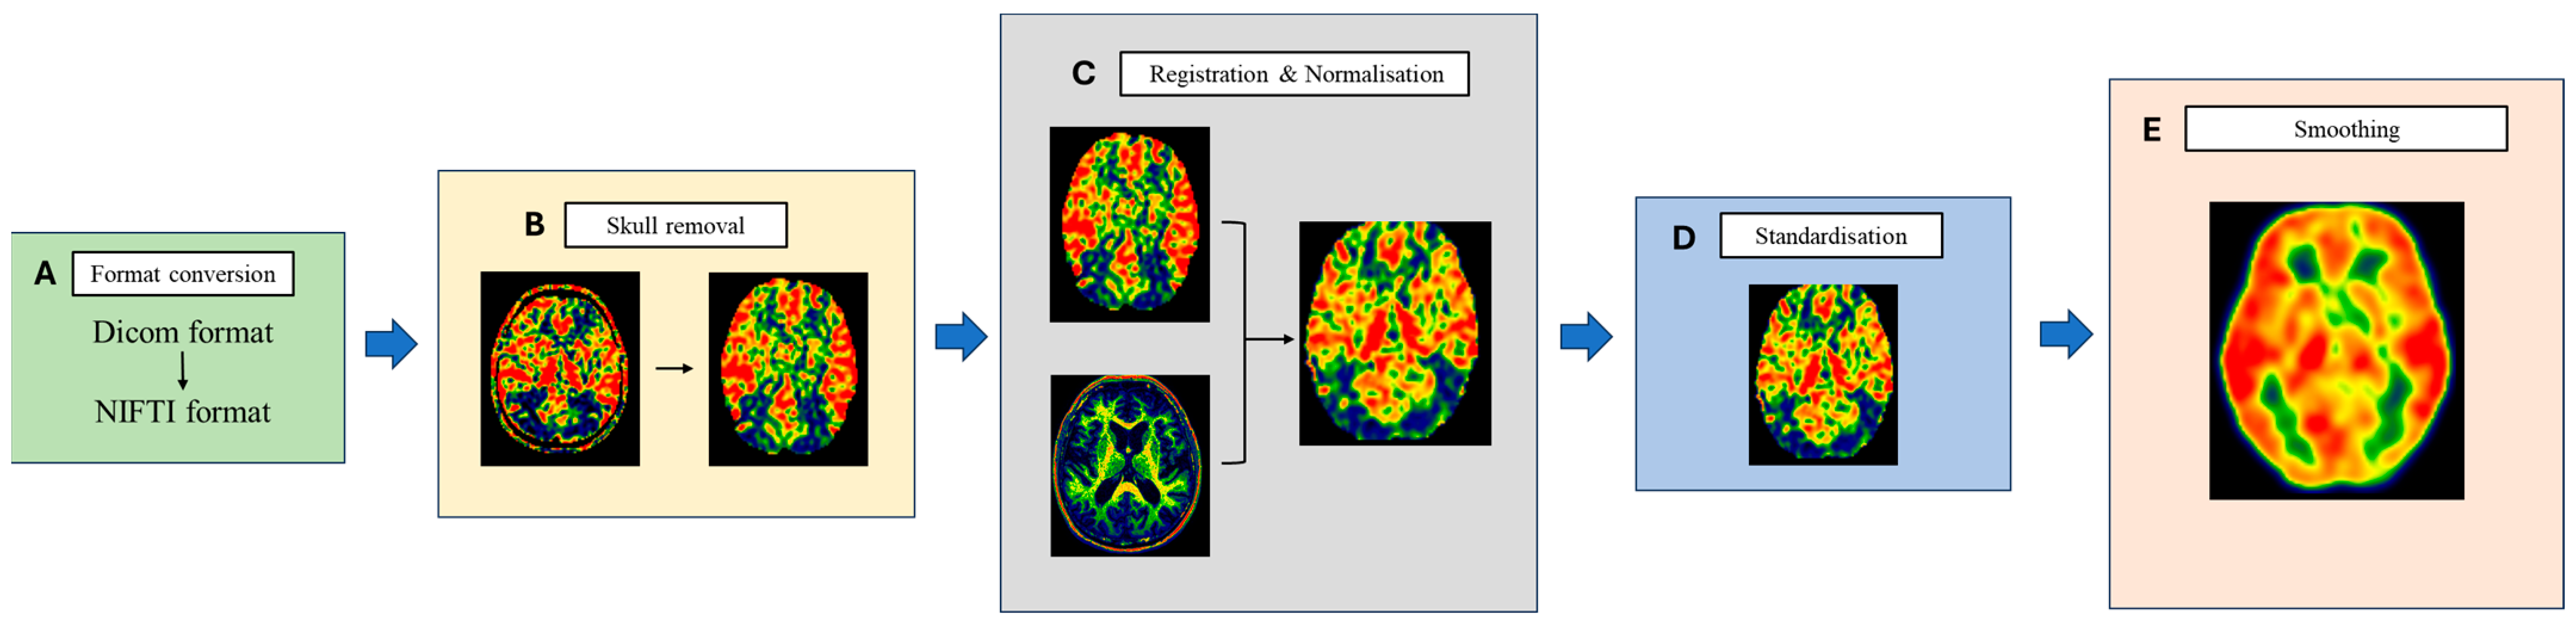

2.5.1. ASL Perfusion Image